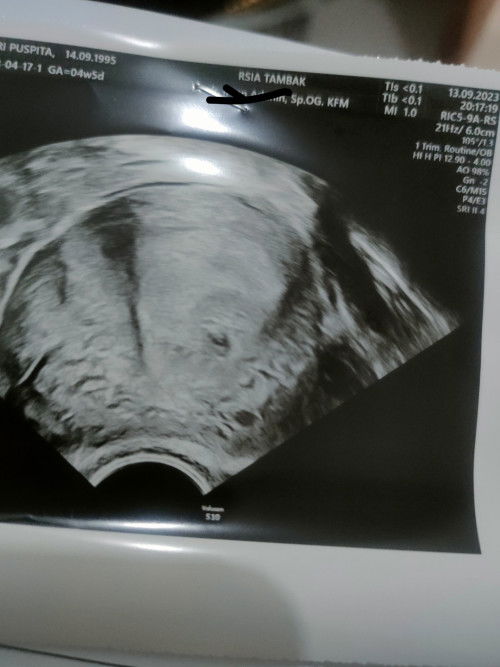

Setelah telat 5 hari dan flek, pagi ini tespek positif. Saya memutuskan utk buru2 ke spog. Mempertimbangkan saya pernah keguguran di Bulan April. Wajar kan bunda? Saya pingin memastikan kali ini kehamilan sy Baik2 aja. Malam ini saya ke rs ketemu spog. Saya malah down. He said, "belum keliatan ini kantungnya, seminggu lagi aja kesini" "bukan tdk ada kehamilan, tp blm keliatan" "mual muntah ada?" Saya jelaskan yg saya rasakan. Beliau malah blg, "maag itu, kalo mual hamil ga begitu" Kok kesannya saya kayak haluuu, pdhl saya udah tespek 3 kali dgb merk beda2, positif semua. Saya jelaskan, 'saya khawatir dokter, krn di april kmrn saya keguguran, mknya saya buru2 ingin tau, apakah saya hrs minum obat penguat kandungan?' Doi jawab,"oh gak gak perlu. Kan saya udah pengalaman, udah biasa yg begini, kita observasi dulu seminggu ini. Sy kasih obat mual sm asam folat" Kesel bundaaaa.. Saya tau beliau sdh pengalaman. Makanya saya dtg ke yg berpengalaman, supaya tenang. Eh malah saya down. Jadi mempertanyakan, beneran hamil gak sih. Kok mual muntahku dianggap sakit maag, pdhl aku gak ada riwayat sakit maag. Ngerasa digampangin. Sediiihhh Adakah yg sama kayak aku? #curhatajabuibu #curhatajabun#bantusharing #seriusnanya #usg #sedih#bantusharing

Hpht 11 Agustus. Sabtu flek coklat, kirain haid. Tp sampe malem ga keluar2 darahnya, ku kirain aku salah liat. mlmnya hb, pas hb agak sakit, trus flek coklat, tak pikir haid. Eh ga keluar2, Selasa respek garis 2 samar. Pagi ini aku respek lagi, garis 2 terang. Mana hari minggunya aku abis fisioterapi. Aman gak ya bund? Kira2 kapan waktu yg tepat aku ke spog? Khawatir juga, soalnya aku ada riwayat abortus april kemarin. Semoga yg skrg sehat ya Allah. #bantusharing #usg #pernahkeguguran

Jadi gini, hr jumat siang saya flek coklat campur keputihan, malamnya berubah jadi merah+gumpalan darah 1cm. Untuk pertolongan pertama, jam 21.00 saya ke klinik fakhira, di usg transvaginal, usia kehamilan 5w5d. Diberikan obat penguat kandungan utrogestan dan bedrest .#seriusnanya #bantusharing #firstbaby #pleasehelp #pendarahan #bleeding Jam 23.00 ,pendarahan nya lbh banyak, keluar gumpalan besar seperti foto pertama. Sampai skrg saya msh pendarahan, seperti haid hari ketiga (foto kedua). Apa ada yg pernah spt saya?. apa kandungan saya masih aman / tidak. Krn blm ada tanda2 pendarahan berkurang.